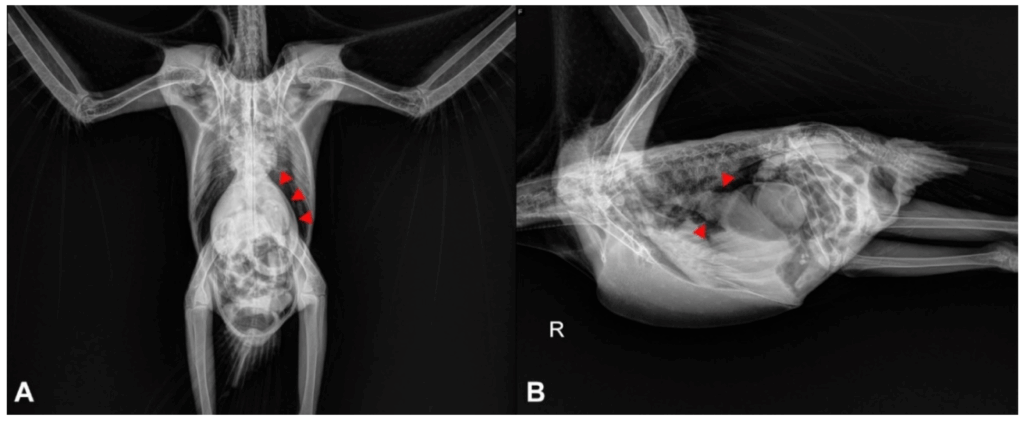

- Fase terminal: dilatação do proventrículo visível em radiografias.